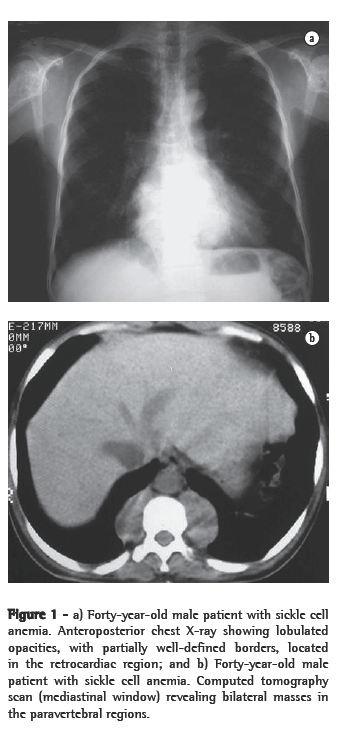

ResultsOf the six patients evaluated, four presented lower paravertebral masses. In three cases, the masses were bilateral and relatively symmetric, and, in one, the mass was unilateral (on the right). Regarding the content of the masses, the presence of adipose tissue was confirmed in three patients, and, in one of them, the quantity of adipose material was quite significant. In one patient, the masses were homogeneous, with dense soft parts (Figures 1a, 1b, 2a and 2b).

Radiographically, intrathoracic EMH usually presents as multiple paravertebral masses, with dense soft parts, usually bilateral, lobulated, with well-defined borders, and without accompanying calcifications or bone erosion.(1,4,5,9) This is important for the differential diagnosis of paravertebral neurofibromas, which usually have accompanying bone alterations.(4,10) However, evidence of bone lesions related to the underlying disease is a common finding. On chest X-rays, such masses usually present an aspect of lobulated, double-contour cardiac silhouette in frontal view, as well as an aspect of a lobulated mass projected over the lower vertebral bodies in profile.(13)